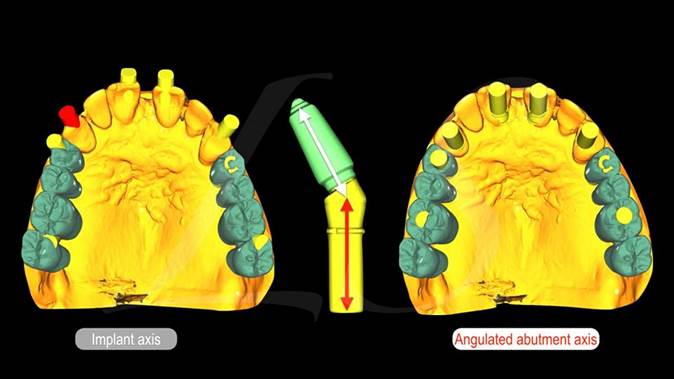

Clinical case: Full-arch implant treatment with immediate loading & extraction implantation

- Courtesy of Dr. Laurent Sers, France -

AnyRidge, R2GATE, guided surgery, Dr. Laurent Sers, immediate loading, maxilla

AnyRidge implant system, R2GATE, Digital prosthesis